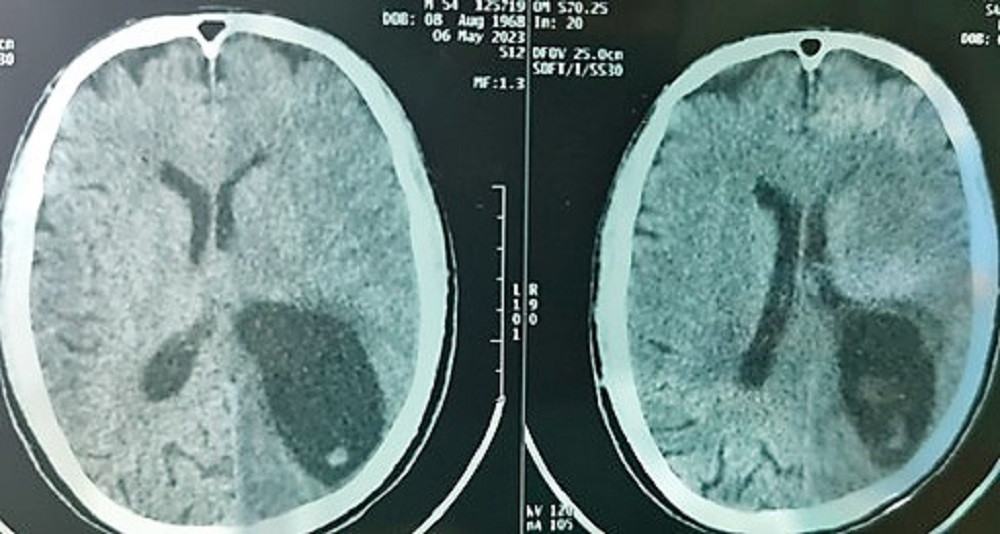

Bệnh nhân đã làm các xét nghiệm phân tìm ký sinh trùng (+), xét nghiệm Elisa chẩn đoán ấu trùng sán lợn Cysticercosis(+), chụp cắt lớp vi tính não cho thấy có nhiều ổ giảm tỷ trọng kèm phù não lớn vùng bán cầu trái.

Sau hội chẩn, các bác sĩ chẩn đoán bệnh nhân bị hội chứng tăng áp lực nội sọ do ấu trùng sán dây lợn trên hệ thần kinh, nguy cơ tử vong cao nếu không xử lý kịp thời.